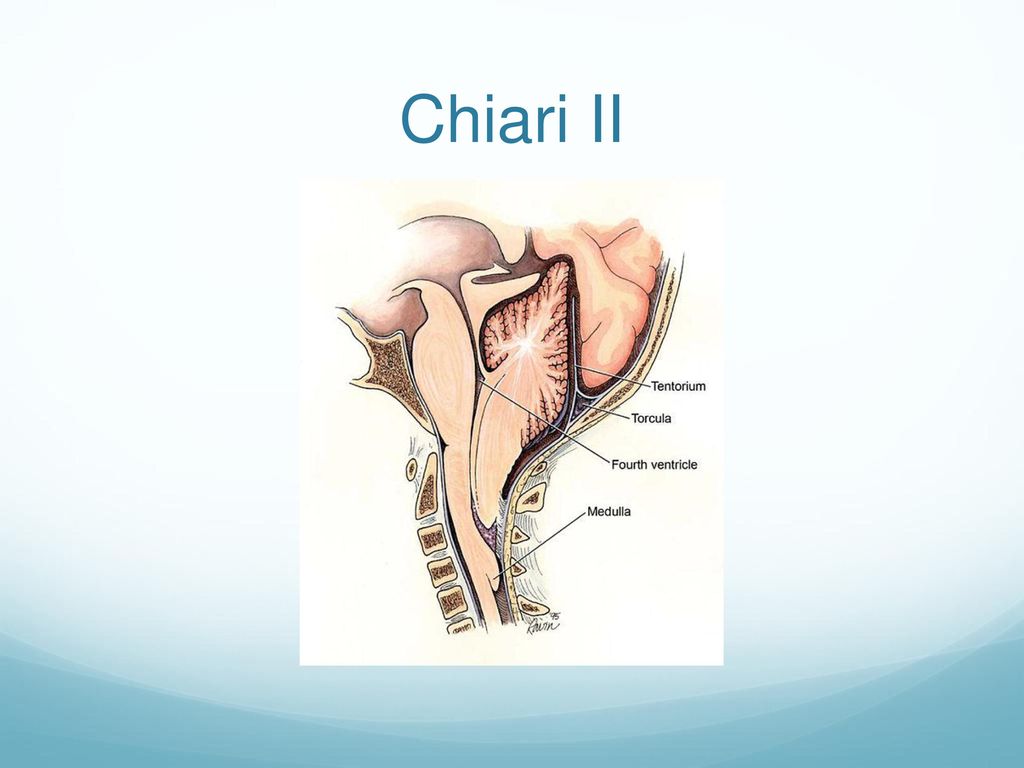

Аномалия Арнольда-Киари: MRI снимки